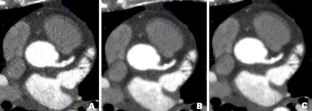

Fig. 1

Fig. 2

Fig. 3